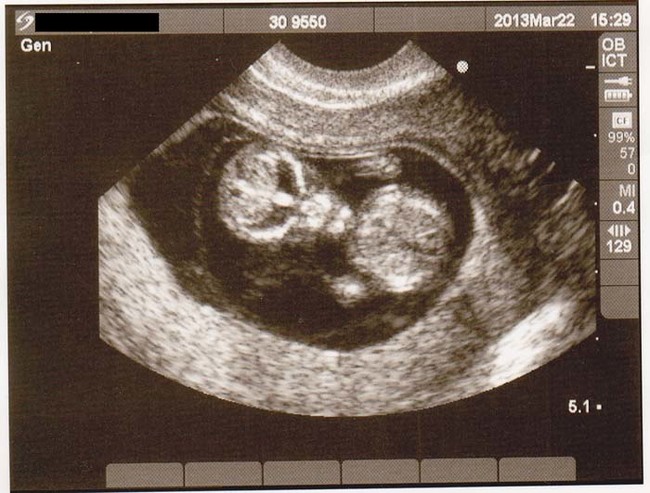

เดี๋ยวนี้ยามตั้งครรภ์คุณแม่เกือบทุกคนก็นิยมอุ้มท้องป่อง ๆ ไปให้คุณหมอทำอัลตราซาวด์ จะได้เช็กดูว่าเจ้าตัวน้อยข้างในอยู่สบายแข็งแรงดีหรือเปล่า แถมยังได้จะเห็นไปหน้าเค้าโครงใบหน้าลาง ๆ ของเจ้าหนูด้วย ดูแค่เงาก็เดาไปกันใหญ่แล้วว่าเหมือนใครมากกว่ากัน จนอดใจไม่ไหวอยากรีบคลอดออกมาให้เห็นหน้าลูกน้อยตัวจริงเร็ว ๆ แต่ถ้ามาเจอ 13 รูปอัลตราซาวด์สุดสยอง ที่เรานำมาฝากจากเว็บไซต์ boredomtherapy เหล่านี้เข้าไปหน่อยล่ะก็... บางทีคุณอาจไม่แน่ใจแล้วล่ะว่า นี่ใช่ลูกฉันจริงหรือเปล่า !!

ถึงจะรักเด็กแค่ไหน แต่ถ้าคุณขวัญอ่อนเราขอเตือนกว่าอย่าเลื่อนลงไปดูดีกว่านะ...